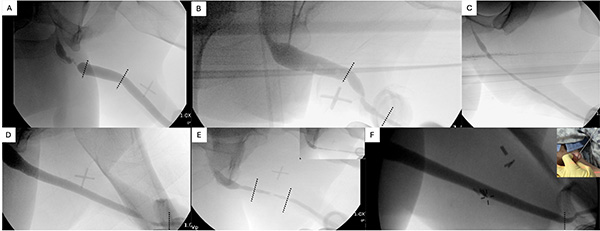

Retrograde urethrogram (RUG): Retrograde urethrogram is an X-ray of the urethra. X-ray dye (also called contrast) is injected into the urethra before the X-ray is taken. The X-ray images show the location, length, and severity of the stricture. It can help you and your surgeon pick the right treatment option.

Images below: Performance of the retrograde urethrogram

Image below: X-rays obtained from the retrograde urethrogram: These X-rays show how stricture length and location can vary by patient. These variations will help your surgeon determine which type of repair will work best for you.